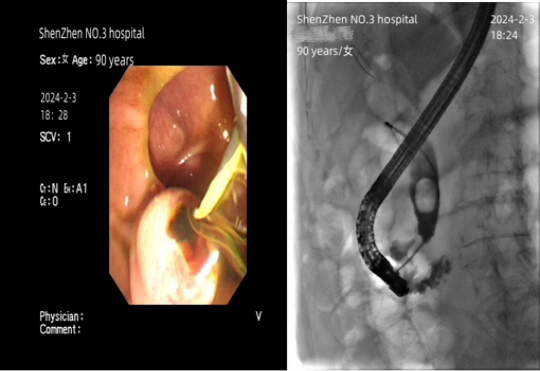

术后第2天恢复清醒即可进食大年三十将出院回家过年

ERCP术,即经内镜逆行胰胆管造影术,是微创治疗胆胰疾病的最佳选择。相对开腹手术而言,ERCP术有无需麻醉、创伤小、恢复快的优势,是郑奶奶最适合的治疗方式。对于石德红而言,这台手术有“急”、“难”、“危”特点。

消化内科ERCP团队迎难而上,由从事ERCP术28年之久、临床经验丰富的石德红担任术者,用时仅仅20分钟就完成了手术,从郑奶奶体内抽出200多毫升脓液。“这台ERCP术比平时做得更快,是因为我们要抢时间。”石德红说。